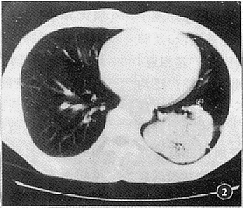

, 百拇医药 2.3 病变形态:球形肺炎多呈尖端朝向肺门的楔形密度增高影,21例中有17例(80%),不规则高密度影2例,类圆形高密度影2例。病变多位于肺野外围,21例中有20例(95%),其外缘与胸膜以广基相连,其间无正常肺组织可见(图1)。周围型肺癌则呈类圆形或卵圆形高密度影,其中类圆形12例(57%),卵圆形9例(43%)。形态均不规则。除2例巨大病灶其外缘与胸膜以广基相连外,余病灶与邻近胸膜间均部分或全部有正常肺组织相隔(图2)。

图1 左肺上叶尖后段球形肺炎,病变呈楔形,与邻近胸膜广基相连,两者间无肺组织可见,病变与肺门间有一较粗大的血管